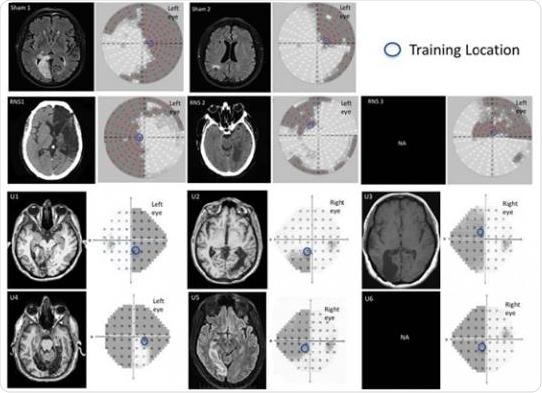

Neuroradiological images and visual perimetries of CB patients. All patients sustained damage of early visual areas or the optic radiations resulting in homonymous visual field defects as shown by the visual field perimetries, next to each brain image. Credit: Herpich et al., JNeurosci (2019)

Lorella Battelli at the IIT-Istituto Italiano di Tecnologia and collaborators Krystel Huxlin and Duje Tadin at the University of Rochester demonstrate enhanced learning in healthy men and women with only 10 days of training. Transcranial random noise stimulation of early visual areas resulted in twice as much improvement on a visual motion task compared to other stimulation techniques or training alone. Surprisingly, the study found this enhanced learning persists for at least six months.

By extending their findings to patients who suffered a stroke or traumatic brain injury affecting their visual cortex, the researchers suggest this safe and painless two-pronged approach could lead to faster visual recovery and improved quality of life for this underserved patient population.